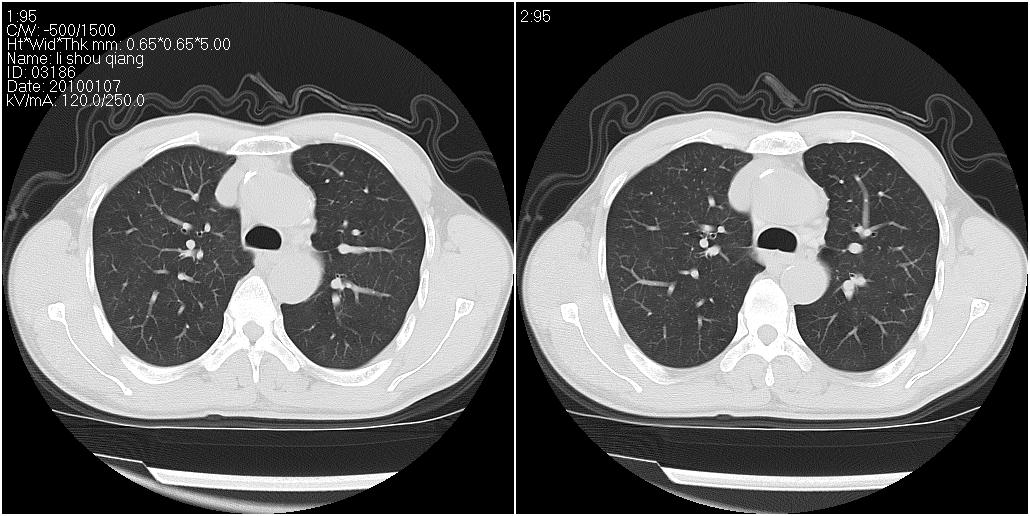

标题: CT24038:男性,58岁。主因咳嗽带血性CT检查。 [打印本页]

标题: CT24038:男性,58岁。主因咳嗽带血性CT检查。

右肺中叶外侧段见一不规则的软组织肿块,边缘可见毛刺,并见厚壁空洞,与胸膜分界欠清。另左下肺见多个小囊状扩张区

右肺中叶外侧段可见团块影,外形不规则,内见空泡征。左下肺见蜂窝状低密度透亮影,部分层面主动脉旁瘤样突出。考虑右肺中叶外围型肺癌可能性大,左下肺支气管扩张,主动脉弓瘤样突出。

1、右肺中叶病灶内不规则气体影、低密度影,且与胸膜接触面宽,病灶边缘模糊。考虑右肺中叶感染并有脓肿形成。建议抗炎治疗后复查。2、左下叶支气管扩张症。

1)考虑右肺中叶周围型肺癌并癌性空洞形成。2)左肺下叶支气管扩张可能性大。

1、右肺中叶病灶周围有炎性反应,所以考虑感染病灶,建议增强扫描进一步鉴别 2、左肺支扩